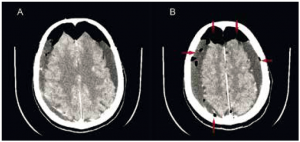

Un cerveau « aéré » : le cas de Mme C., 77 ans

Mme C., 77 ans, est adressée à l’hôpital pour confusion dans un contexte de multiples chutes avec traumatisme crânien, impossibilité de se relever seule et troubles de l’équilibre... Antécédents Parmi…